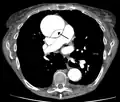

Ultrasound

An echocardiogram displaying the true lumen and false lumen of an aortic dissection: In the image to the left, the intimal flap can be seen separating the two lumens. In the image to the right, color flow during ventricular systole suggests that the upper lumen is the true lumen.

The transesophageal echocardiogram (TEE) is a good test in the diagnosis of aortic dissection, with a sensitivity up to 98% and a specificity up to 97%. It has become the preferred imaging modality for suspected aortic dissection. It is a relatively noninvasive test, requiring the individual to swallow the echocardiography probe. It is especially good in the evaluation of AI in the setting of ascending aortic dissection and to determine whether the ostia (origins) of the coronary arteries are involved. While many institutions give sedation during transesophageal echocardiography for added patient comfort, it can be performed in cooperative individuals without the use of sedation. Disadvantages of TEE include the inability to visualize the distal ascending aorta (the beginning of the aortic arch), and the descending abdominal aorta that lies below the stomach. A TEE may be technically difficult to perform in individuals with esophageal strictures or varices.